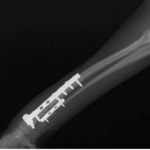

トイプードル 右遠位橈尺骨短斜骨折のALPSによる内固定

LCPは、スクリュー(ネジ)とプレート(金属の板)をロックする特殊な構造により骨折部位を固定する新しい世代のプレートシステムです。ひとつのホールでロッキングスクリューとスタンダードスクリューの使用を選択できるユニークな構造をしているため、骨折断端間の圧迫を目的とした従来型プレート固定法に加え、高い角度安定性を有するロッキングスクリューを用いた固定法の選択が可能です。従来のプレートシステムでは困難だった部分の骨折や癒合不全の症例に高い治療効果をもたらします。

当院ではAdvanced Locking plate system(ALPS)と、Locking compression plate system(LCPS)という骨接合法で骨折症例の治療を行っています。

7.1.5mmと薄いプレートのため、超小型犬にも使用しやすい

8.抜去が不要となることが多い